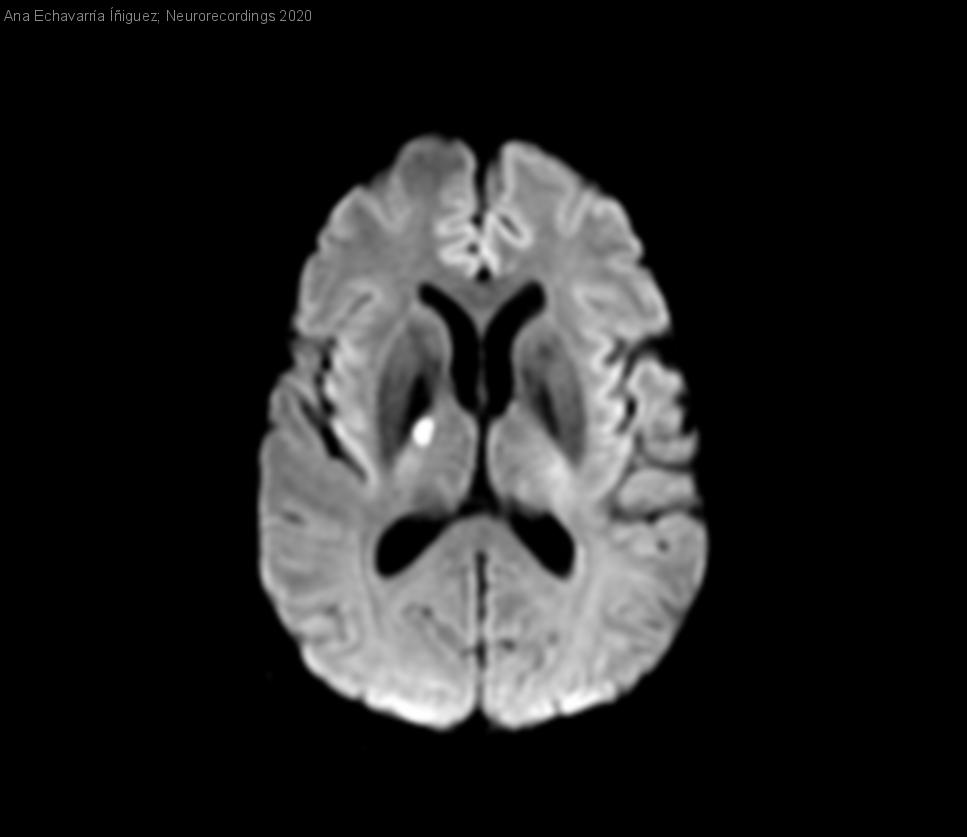

Hombre | 49 años

Diagnóstico final: Enfermedad diseminada por Cryptococcus neoformans (meningoencefalitis y diseminación hematógena). Infección por VIH.

Varón 49 años, consumidor de cannabis y hachis, fumador de 20 cigarrilos/día, sin otros antecedentes de interés. Presenta cuadro de cefalea holocraneal de una semana de evolución, afasia motora de horas de evolución, febrícula e...